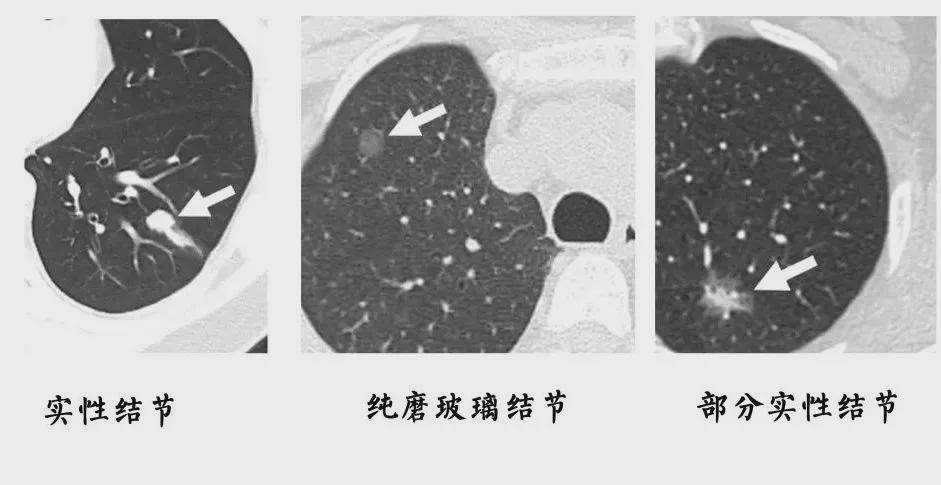

结节一般是指在CT、彩超、磁共振等检查中发现的直径小于3厘米的病灶 。

医生会根据结节的形状、密度、血液供应等特点 , 来初步判断这些结节的性质 。

虽然多数的结节为良性 , 但也有些结节是恶性肿瘤的前期表现 , 一旦检出 , 应该密切复查 , 及时干预治疗 。